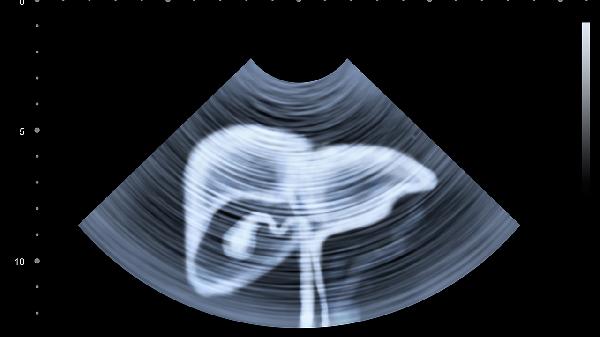

女性盆腔炎或卵巢囊肿蒂扭转会在腹部用力时加重盆腔充血,表现为下腹坠痛。需通过妇科超声和分泌物检查鉴别,急性炎症需使用头孢曲松联合甲硝唑抗感染,囊肿直径超过5厘米建议腹腔镜手术。